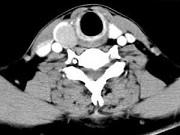

问题 男,43岁,右颈部扪及一包块,CT如图所示,应诊断为()

选项 A.甲状腺腺瘤 B.甲状腺腺癌 C.结节性甲状腺肿 D.甲状腺原发淋巴瘤 E.甲状腺转移瘤

答案 A